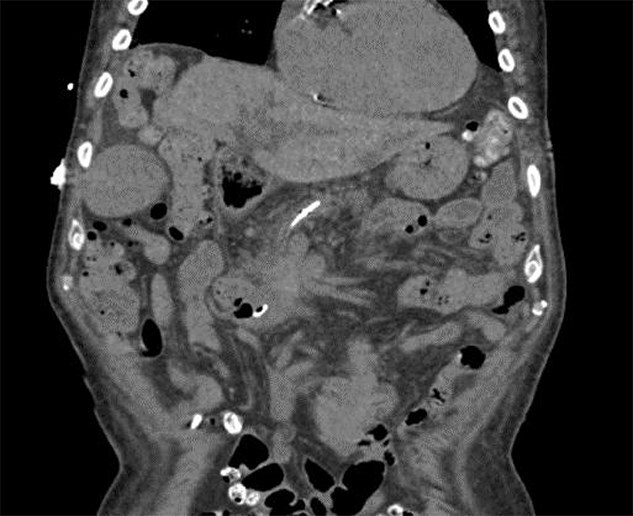

Rhabdomyolysis is a clinical syndrome characterized by the breakdown of skeletal muscle tissue, leading to the release of myoglobin and creatine kinase (CK) into the bloodstream. The condition clinically presents with myalgia, weakness, and dark urine. It can lead to kidney failure and can be life threatening. Various factors and conditions, including trauma, prolonged immobilization, strenuous exercise, infections, alcohol consumption, medications, and malignancies are potential causes. A rare cause of pancreatic cancer-induced paraneoplastic myositis has been observed. Herein, we present the case of an 87-year-old man who presented with fatigue, weight loss, and invasive pancreatic adenocarcinoma resulting in rhabdomyolysis due to paraneoplastic myositis.